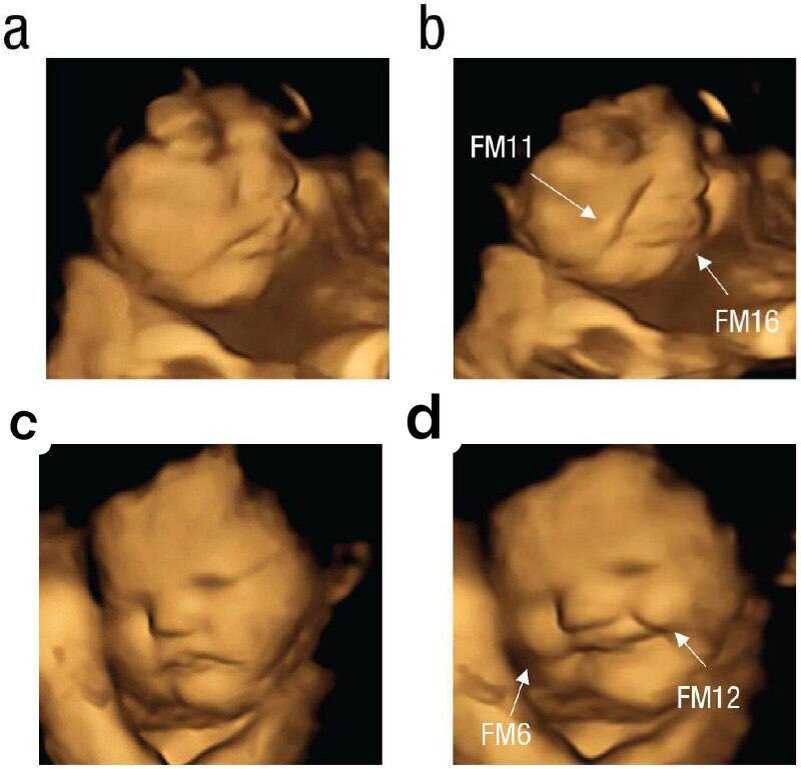

После принятия капсул был проведен покадровый анализ движений лица плода и выяснилось, что ребенок в утробе плакал в два раза чаще, когда мама употребляла капусту, в сравнении с морковкой.

a,b - мать ела капусту, c,d - морковку

Более того, морковь нравилась всем и выражение лица было похоже на смех.